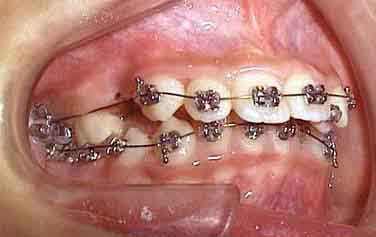

治療開始6ヶ月

治療開始1年後